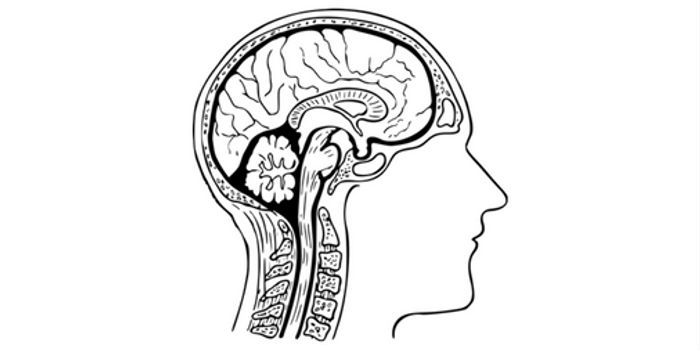

Read the latest articles about newly released neuroscience research and advances in experimental techniques. Topics include research news in neuroscience, neurology, psychology, brain science and cognitive sciences.